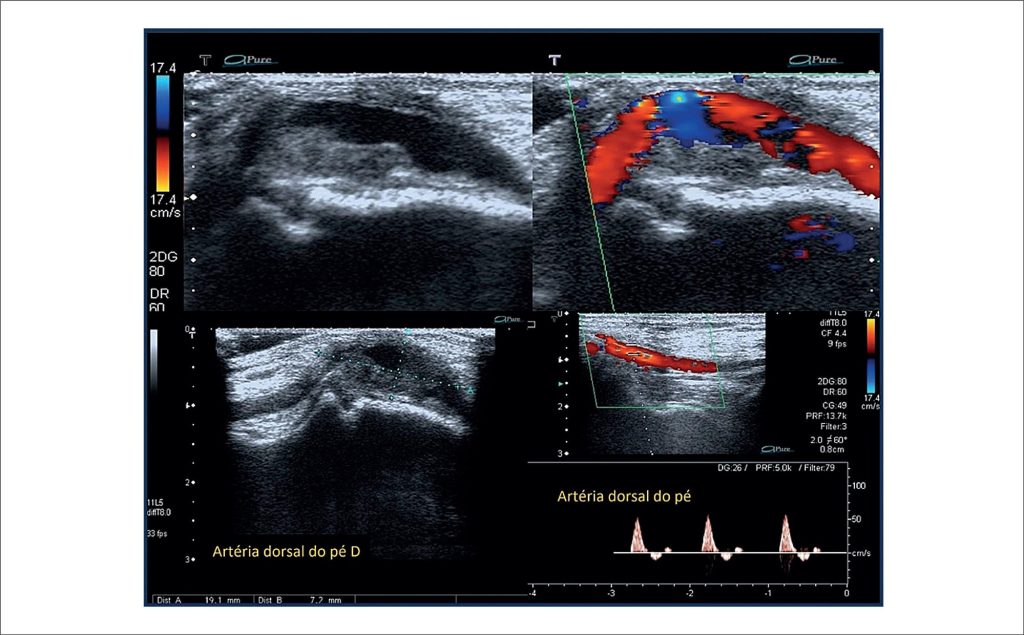

Dorsalis Pedis Artery Aneurysm: an Ultrasound Diagnosis

The DPAA (pedal artery) was first described in 1907. Since then, other authors have reported this rare type of aneurysm, but its clinical manifestations are still relatively unknown. With only 24 cases reported in the literature until 2017, according to Aragão et al., the DPAA aneurysm is more common among men (63%) with a mean age of 55.4%. In general, it appears as a pulsatile mass, which may lead to microembolization, hemorrhage, rupture, and nerve compression. Physical examination usually reveals a pulsatile mass that can cause pain, paresthesia, and discomfort when walking or wearing shoes, complaints similar to the case reported in our study.